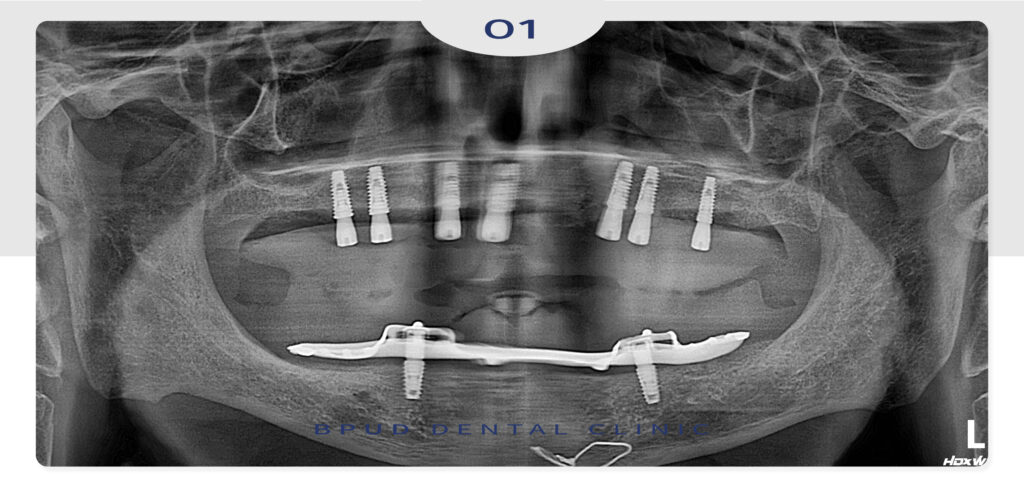

사진에서 보는 것과 같이 오른쪽 위 송곳니의

우식으로 부러진 상태였고 뒤쪽의 작은 어금니들은

치근단 병소도 확인되고 동요도가 있어

세개 치아 모두 발치 후 총 7개의 임플란트를 식립하여

전체 임플란트 보철 수복을 계획하였습니다.